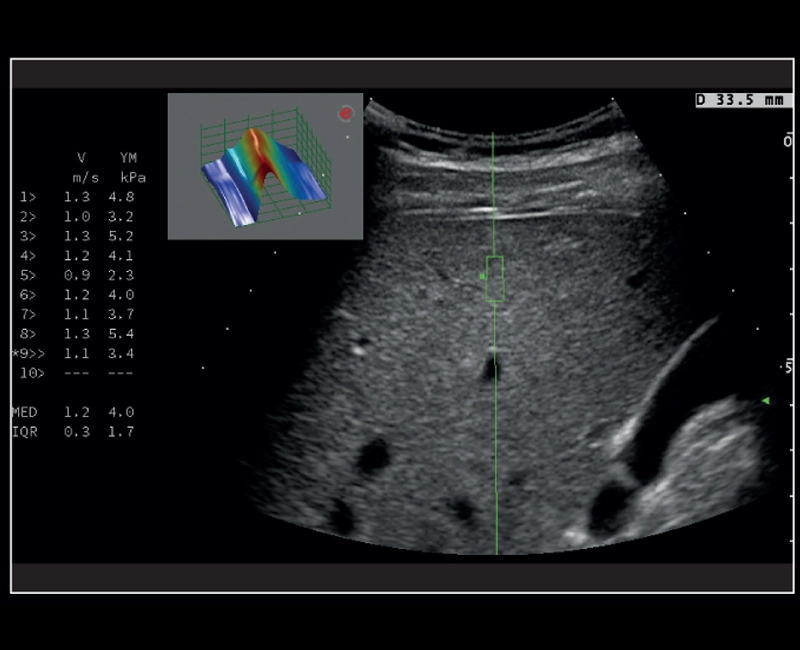

MyLab™9 Platform - QElaXto point Shearwave Elastography in liver

MyLab™9 Platform - QElaXto point Shearwave Elastography in liver